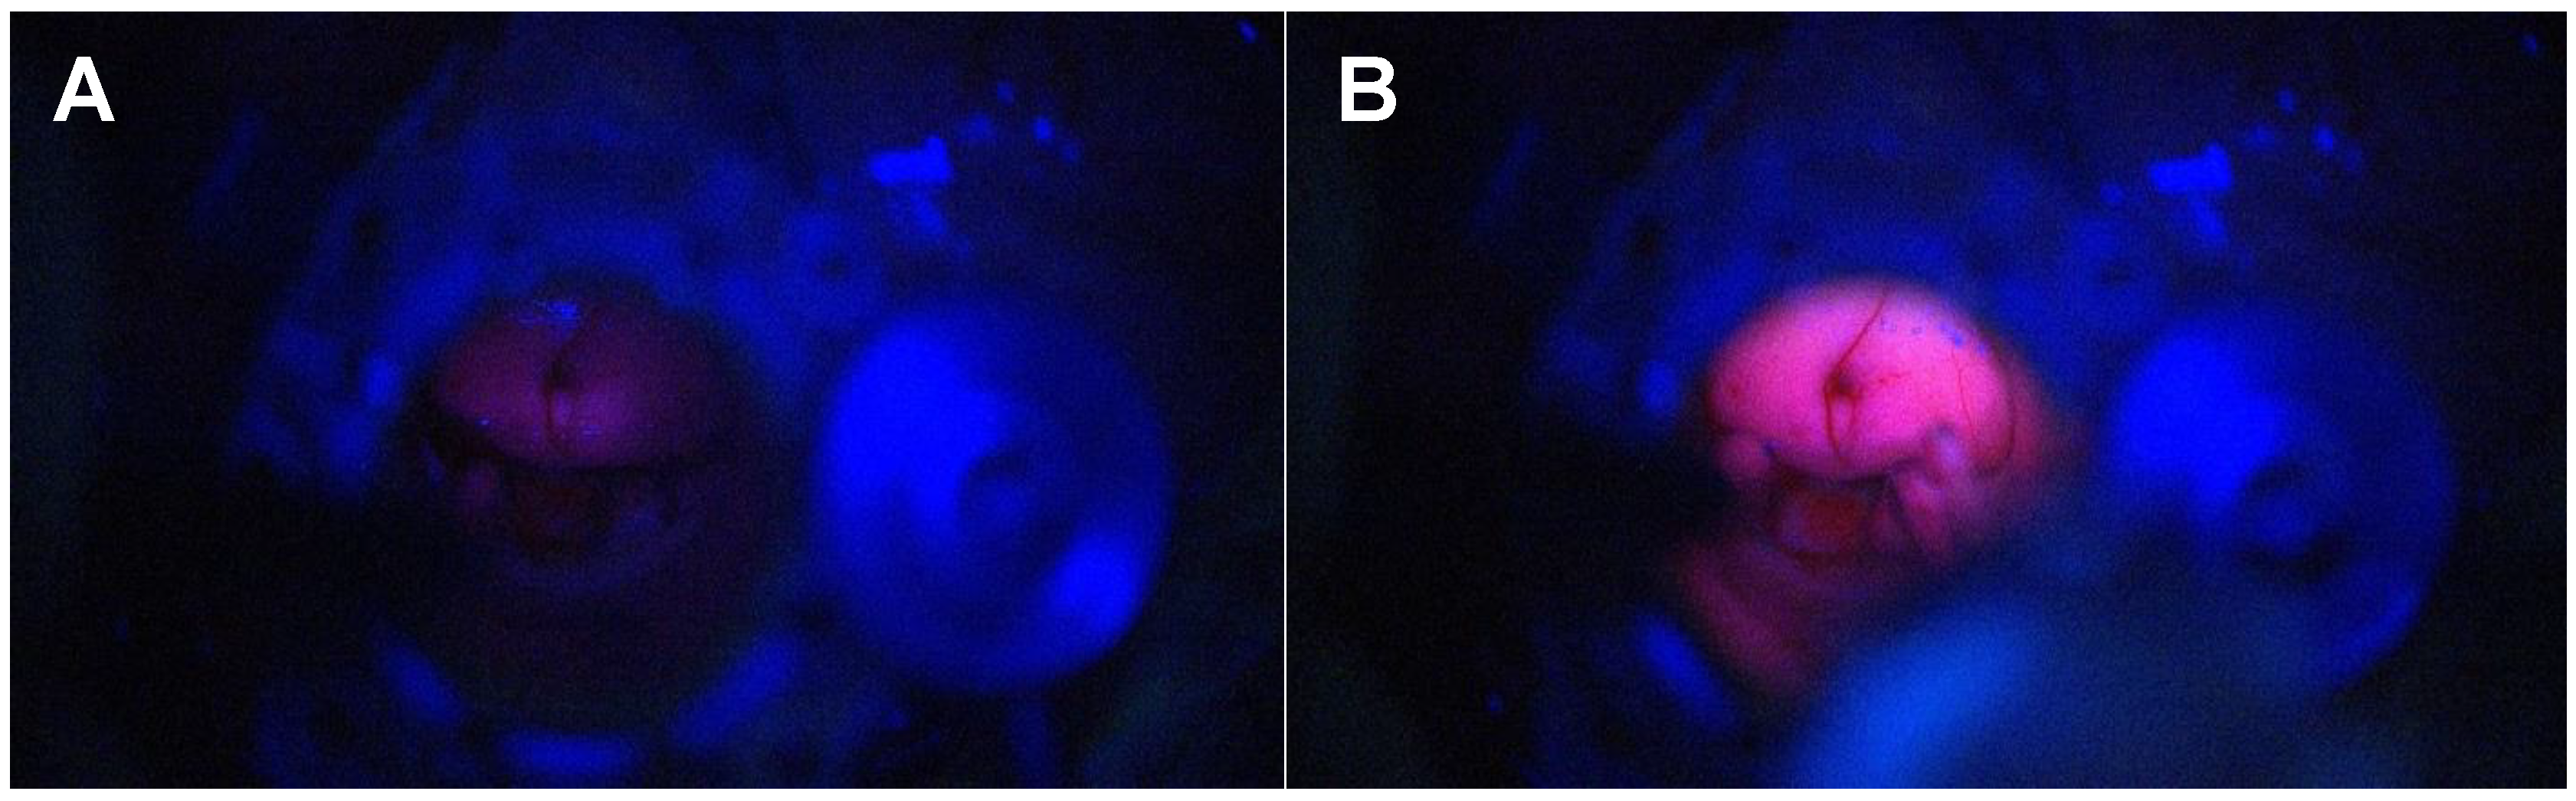

3.1.4. Differentiation Between Necrosis and Recurrence in Redo Surgery

3.1.5. Identification of Normal Ependyma Versus Pathological Ependymal and SubepenDymal Tissue